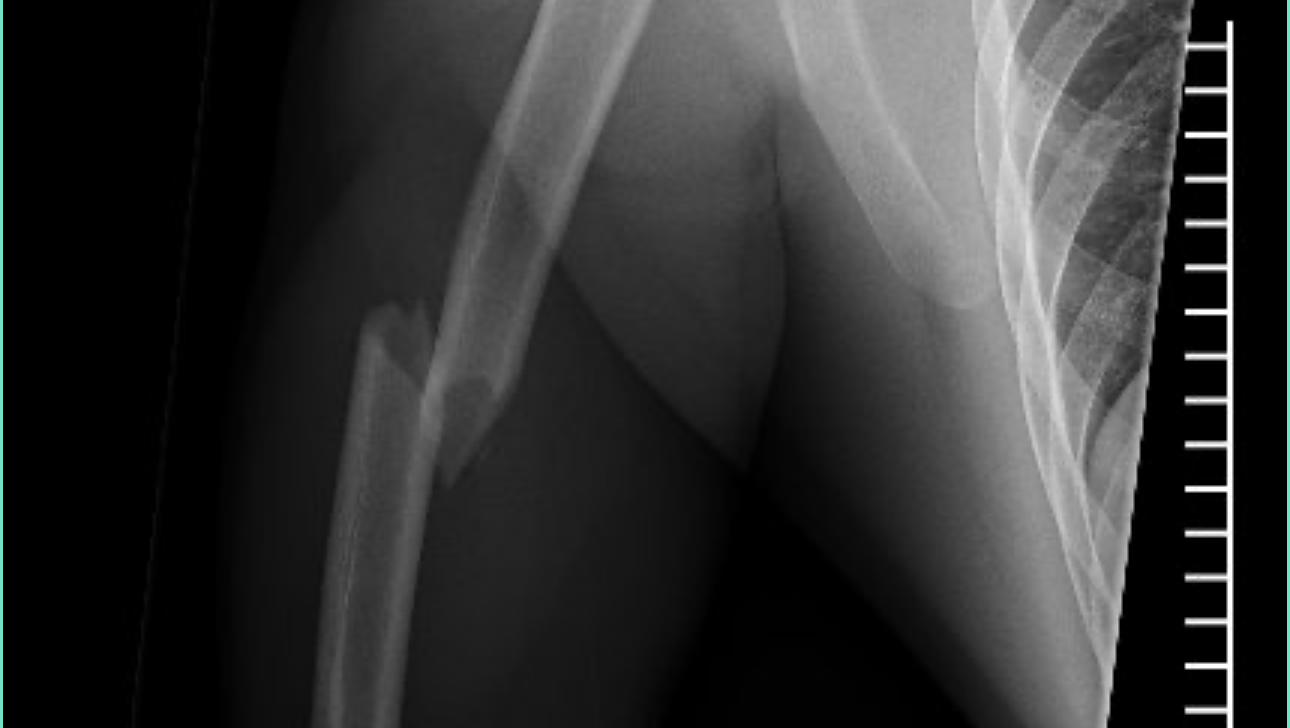

Once at the hospital, it was determined that he broke both of his arms and legs in multiple places, shattered his knee cap, broke his ribs, broke and dislocated his hip, and broke his femur. The only thing not broken is his spirit, pretty face, and desire to face this battle head on. Despite only being able to wiggle his fingers and toes, he still keeps us and the wonderful hospital staff laughing and is a true inspiration.

Brandon has been hospitalized since the accident and following multiple surgeries and some gnarly titanium all throughout his body, he is preparing to go to a rehabilitation center/nursing home to continue healing with months of physical therapy as he is not anywhere near being self-sufficient.